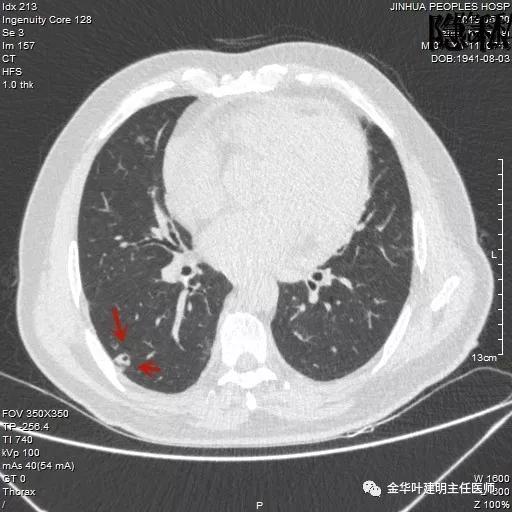

以上是2016年5月的片子,此处有非常小而淡的空腔性病灶,边缘略显磨玻璃,但仍说不上肯定的恶性。